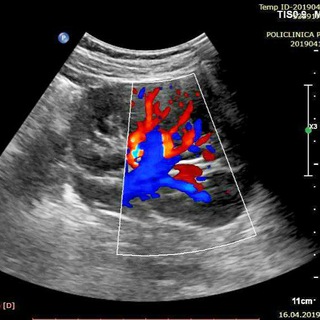

УЗД Атлас. Atlas of Ultrasound. Ультразвуковые сканы

Ультразвуковые сканы иследований с описанием.